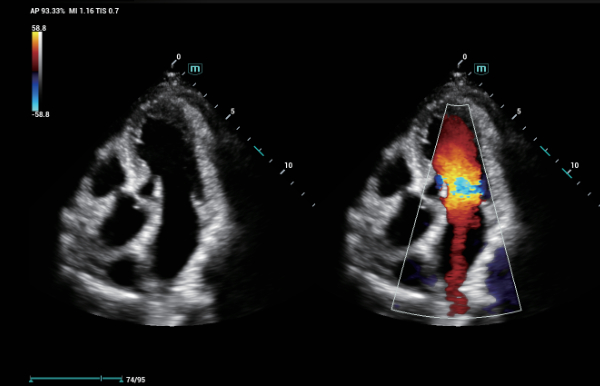

Indipendentemente dalle attività svolte in ospedale o in clinica, oppure se si desidera affinare le proprie capacità nella diagnostica per immagini generale negli ambiti della salute della donna o cardiovascolare, questa serie di soluzioni fornirà potenti strumenti per essere sempre un passo avanti.

Soluzioni di diagnostica per immagini complete con tecnologia ZST+

La piattaforma ZST+ è un'innovazione straordinaria, che rappresenta un'evoluzione nel campo dell'ecografia. Grazie alla trasformazione delle metriche a ultrasuoni dal beamforming convenzionale all'elaborazione basata sui dati di canale, supera la tradizionale limitazione del trade-off tra risoluzione spaziale, risoluzione temporale e uniformità dei tessuti, offrendo una qualità d'immagine eccezionale per infinite soluzioni di imaging con miglioramenti continui.